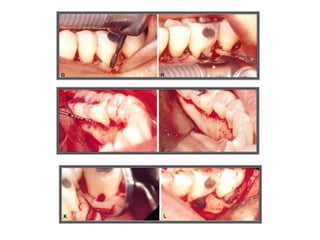

TRATAMENTO DAS LESÕES

ENDOPERIODONTAIS

Rizectomia

DEL RIO, 1996

Rizectomia

ODONTOSSECÇÃO